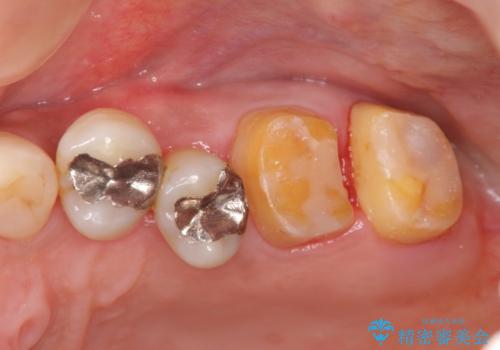

歯周病 側方力に対抗するブリッジ補綴

- 全体的に歯が揺れ、このままでは全て歯を失うのではないかと怖くなり歯周病治療を希望され来院されました。

歯列不正による第一小臼歯の骨吸収が認められ、機能咬合力の回復、大きな側方力に連結することで抵抗することのできるブリッジ補綴を選択しました。

歯周病による深いポケット・大きな側方力・短い臨床歯根・欠損の補綴、これらの問題を解決するために歯周補綴を兼ねたブリッジを選択しました。